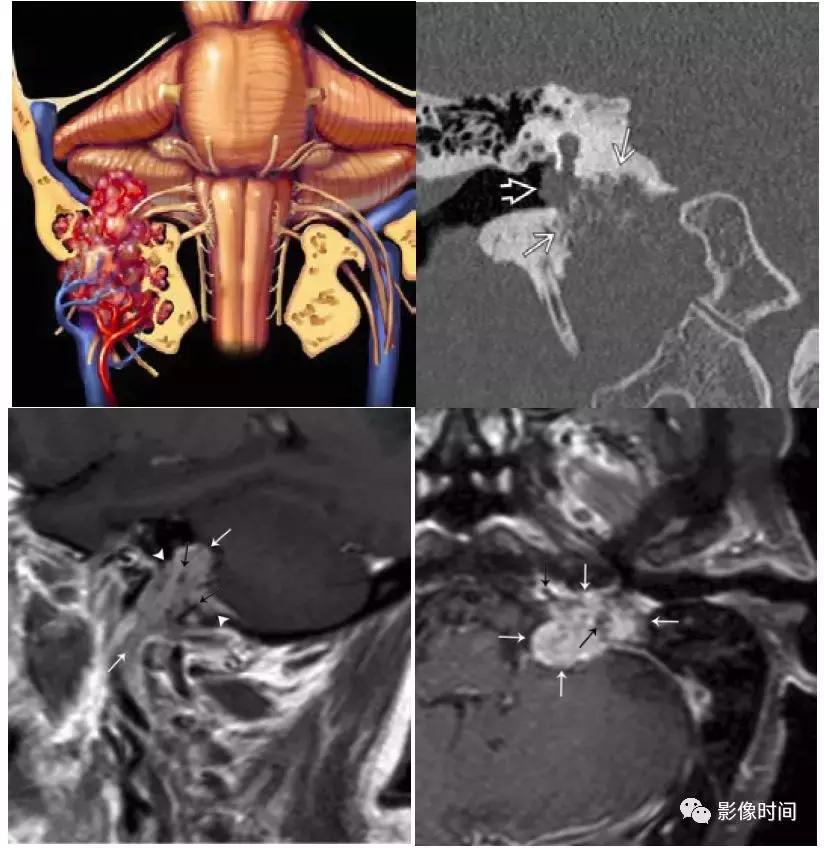

(2).颈静脉球瘤:可发生于舌咽神经鼓室支或迷走神经耳支,50-60 岁男性多见,临床症状多为耳鸣、听力损失或眩晕,和其他与颈静脉孔内的颅神经有关的症状。

模式图显示颈静脉球瘤富含血管,包绕颅神经伴「虫噬状骨质破坏」。CT 显示颈静脉孔区「蛀虫」的骨质破坏。增强 MRI 显示颈静脉孔区增强肿块 (白色箭头),注意流空信号 (黑色箭头)。

3、脑膜瘤:脑膜瘤是中枢神经系统最常见的脑外颅内肿瘤,大多数脑膜瘤发生在颅内。颈静脉孔区的脑膜瘤可向下延伸至颈动脉间隙。大多数脑膜瘤 CT 表现为等或者高密度,20% 钙化,邻近骨质表现为反应性骨质增生。在 MRI 上,脑膜瘤通常表现为 T1WI 等或稍低信号,T2WI 等或稍高信号,明显强化,可见脑膜尾征。

轴位 CT 显示病灶相邻的骨质增生(白色箭头),正常左乳突骨皮质 (黑箭头)。轴位 T2WI 病灶呈等信号 (白色箭头),向前推移颈内动脉 (i)。左侧颈内动脉的正常位置也被观察到。

矢状位 T1WI+C 病灶明显强化 (白色箭头) 从后窝延通过颈静脉孔 (黑色箭头) 延伸至右颈动脉间隙,见硬膜尾征(无尾箭头)。